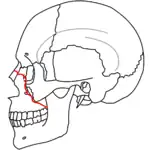

A principios del siglo XX, René Le Fort trazó ubicaciones típicas para las fracturas faciales, éstas ahora son conocidas como I, II y III fracturas de Le Fort (derecha).[5][2][6]

La Fractura de Le Fort#Lefort III, también llamada disyunción craneofacial y fractura facial transversal,[7][11] cruza la parte delantera del maxilar superior e implica al hueso lacrimal, a la lámina papirácea, y a la cavidad orbitaria, y a menudo implica al hueso etmoides,[9] es la más grave.[12] Las fracturas de Le Fort, que representan del 10% al 20% de las fracturas faciales, a menudo son asociadas con otras lesiones graves.[9]

Le Fort hizo sus clasificaciones basadas en el trabajo con cráneos de cadáveres, y el sistema de clasificación ha sido criticado por impreciso y simplista ya que la mayoría de las fracturas del tercio medio facial implican una combinación de las fracturas Le Fort.[9] A pesar de que la mayor parte de las fracturas faciales no siguen los patrones descritos por Le Fort de forma precisa, el sistema todavía se utiliza en la clínica para clasificar las lesiones.[13]